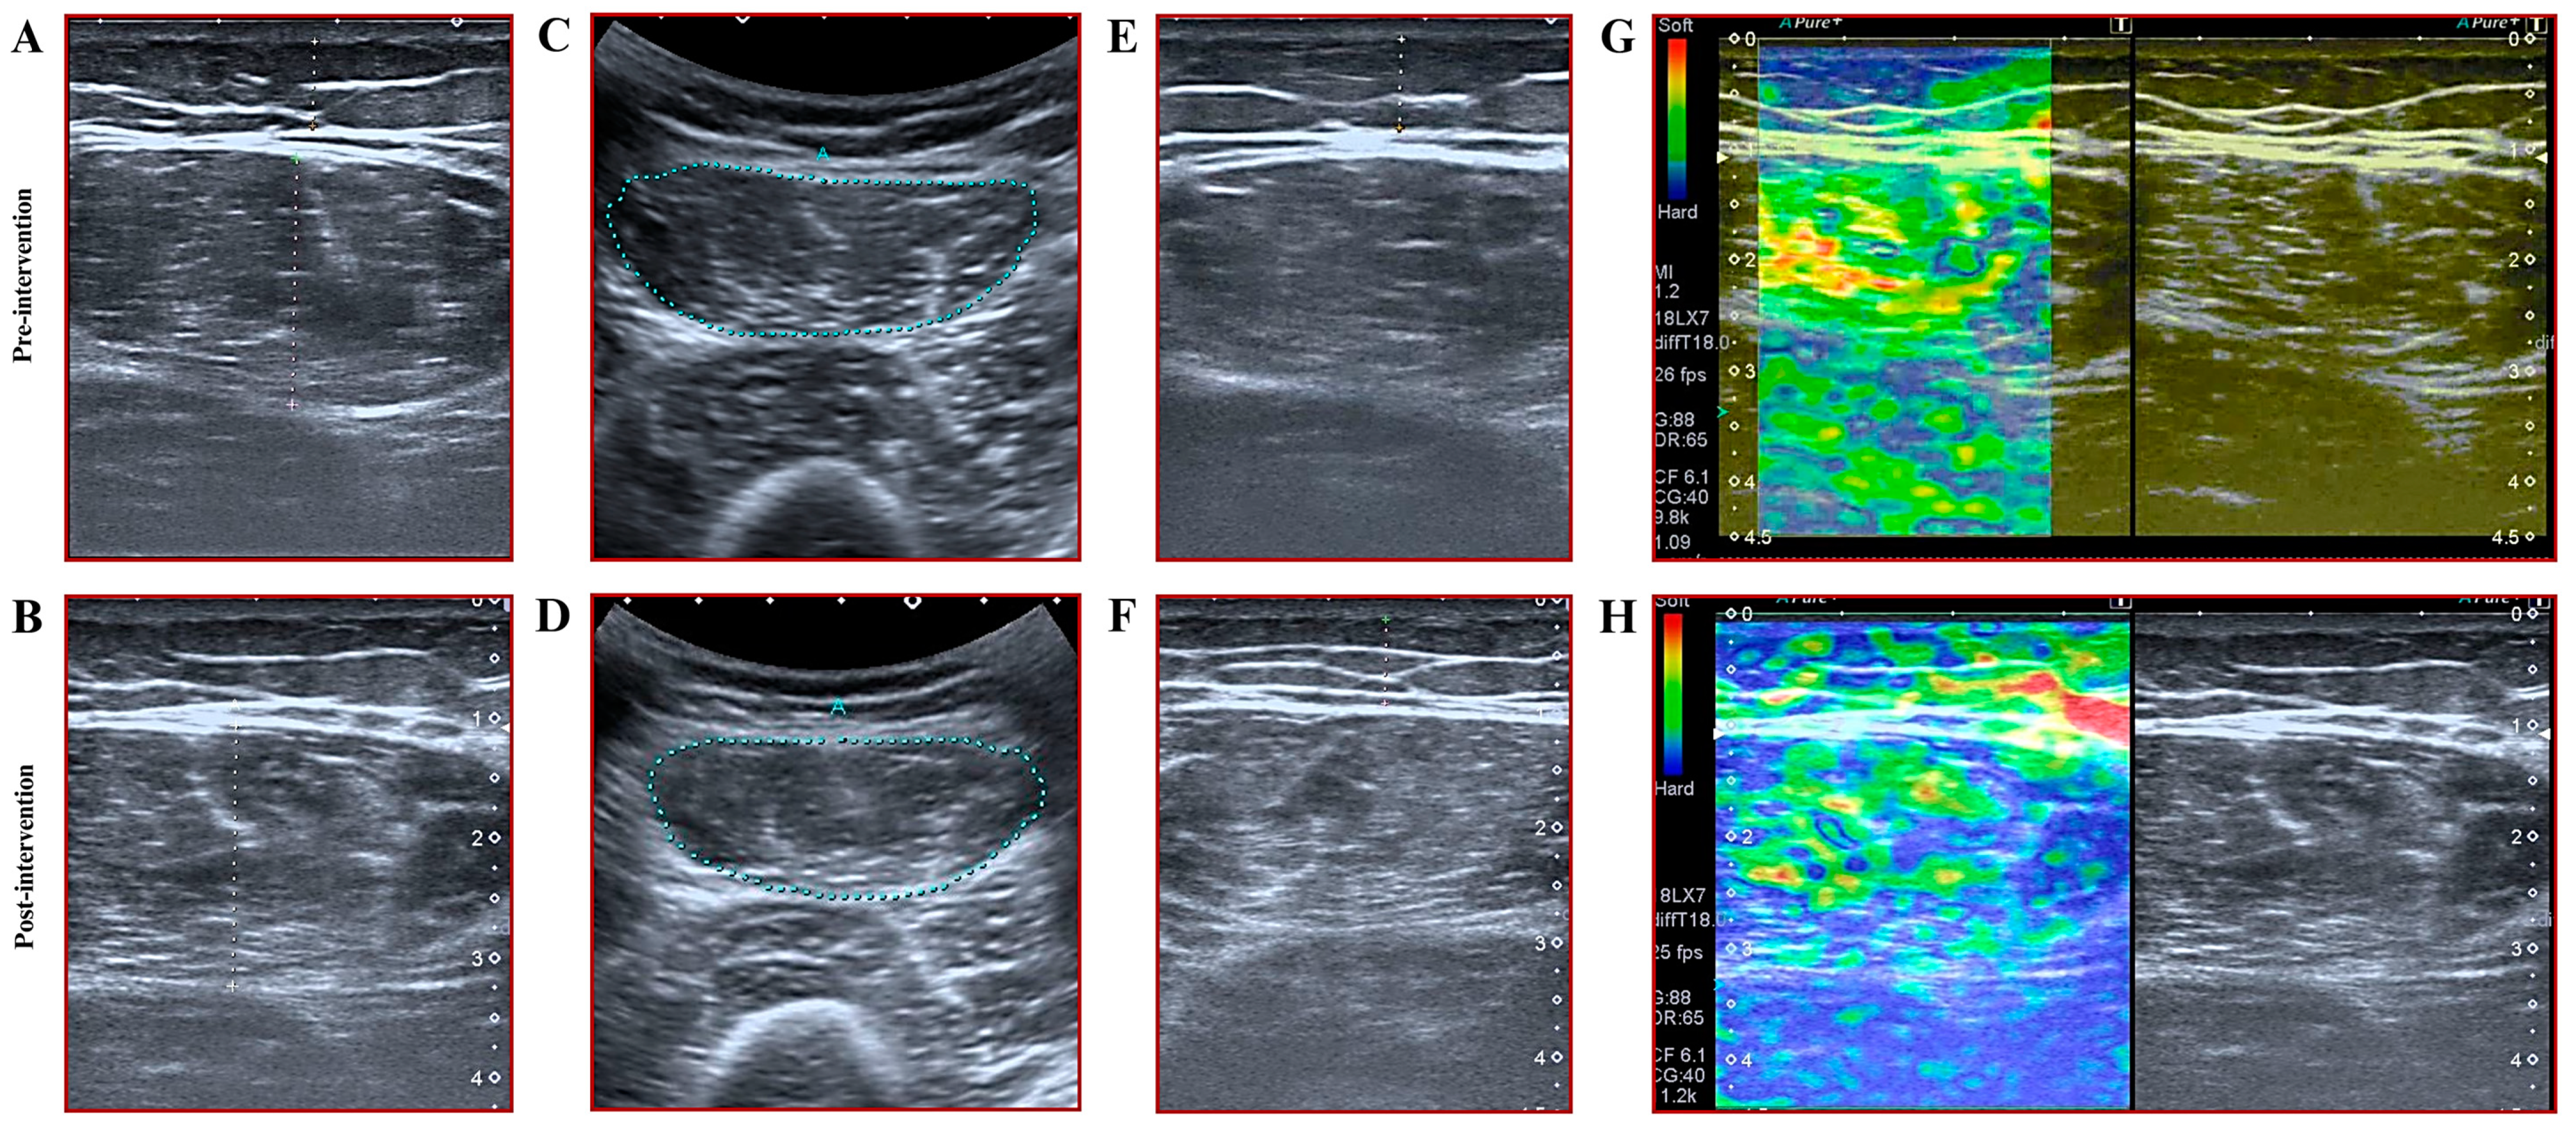

2.2.7. Assessment of Muscle Thickness, Subcutaneous Fat Thickness, and Cross-Sectional Area

2.2.8. Assessments of Muscle Stiffness

3.4. Results for Muscle Thickness, Cross-Sectional Area, and Muscle Stiffness